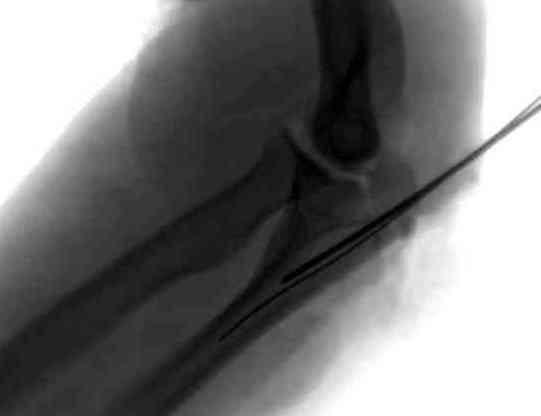

Здесь выставлены несколько случаев и варианты фиксации локтевого отростка, некоторые в комбинации с другими переломами.

3 вариант

перелом с capitelum humerus и проксимальной трети улна